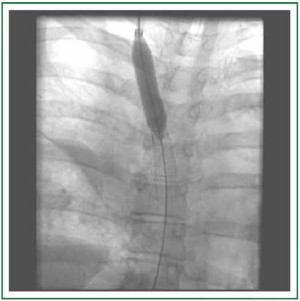

A chest computed tomography demonstrated a 5 cm × 5 cm × 6.5 cm diffuse infiltrative process within the anterior mediastinum, occluding the superior vena cava and extending into the right hilar and subcarinal region (Figure 1). This process engulfed the take-off of all the branch vessels of the aorta and truncus anterior. A Positron Emission Tomography (PET) did not demonstrate any abnormal hypermetabolism in the patient’s body.

Figure 1. Diffuse infiltrative process (indicated by arrows) within the anterior mediastinum extending along the superior vena cava into the right hilar and subcarinal region with calcifications.